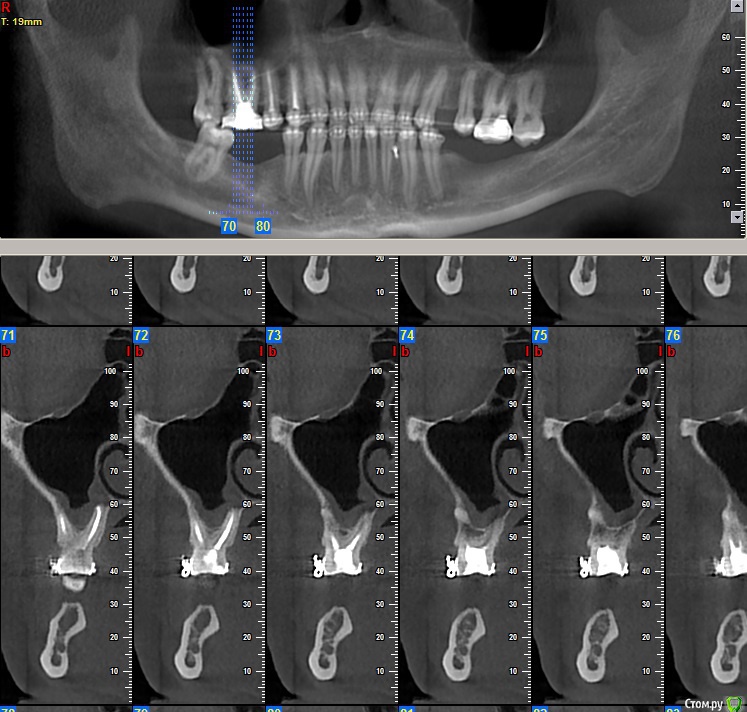

Dionis Опубликовано 13 августа, 2015 Поделиться Опубликовано 13 августа, 2015 Добрый день. Прошел 4х годичный курс лечения ортодонтии. Все готово. Но перед съемом брекетов остро стоит вопрос имплантации. Ортодонт говорит, что нельзя снимать без готовых имплантатов, т.к. могут разъехаться обратно. Прикладываю 4 снимка: до лечения, и 3 снимка КТ с освободившимися местами под имплантаты после лечения. Прошу совета у знающих специалистов:1) В какой последовательности все делать? Очень хочется максимально быстро снять брекеты - сил больше нет(((2) Сколько имплантатов ставить и куда?3) Хватит ли кости справа внизу?4) Посоветуйте, пжста, как выбрать специалиста (-ов), можно в личку. Посетил 3 консультации, две из трех никуда не годятся (доктора не понравились - навязчиво втираются в доверие и ведут себя странно, да и стоимость запредельно выше рыночной). Один доктор понравился, но много негативных отзывов в нете о клинике, как и позитивных, да и видно обилие липовых и левых отзывов, хвалящих самих себя (одни и те же отзывы на разных форумах под разными именами, отзывы с одного айпи и т.д.). Плюс не знаком ещё с ортопедом, который работает в паре... Пока рассматриваю. Буду очень признателен за любую ценную информацию! С уважением,Денис из Москвы Ссылка на комментарий

Dionis Опубликовано 14 августа, 2015 Автор Поделиться Опубликовано 14 августа, 2015 Очень хотелось бы услышать мнения профессионалов по первым трем вопросам:1) В какой последовательности все делать? Очень хочется максимально быстро снять брекеты2) Сколько имплантатов ставить и куда? Ваше мнение очень интересно по поводу нижней челюсти!3) Хватит ли кости справа внизу? Если не хватает, то какой вариант возможен для увеличения (пластика какая именно)? Насколько сложный случай? Судя по КТ, по правому низу в районе 5ки ещё и нерв выходит из челюсти - вчера был на приеме у хирурга, где меня предупредили, что при пластике будет потеря чувствительности из-за разрыва... Насколько это серьезно? Чем чревато в будущем? Совместно с хирургов выработали вариант имплантации 6го с консолью на 5ый. Какие ещё мнения возможны? Спасибо за Ваши ответы,С уважением,Денис Ссылка на комментарий

faity Опубликовано 19 августа, 2015 Поделиться Опубликовано 19 августа, 2015 посмотрел КТ, качество и удобство конечно редкостное...)))проблем не увидел особых, справа импланты, слева импланты и операция по костной пластике. через полгода будете уже ими жевать.только нужно будет КТ переделать, потому что для качественного планирования этого недостаточно.а правильное планирование это половина лечения.по этапам: гигиена(при необходимости), имплантация, через 4 месяца снимать слепки, когда будут готовы коронки- снимать брекеты и фиксировать коронки. но в любом случае надо смотреть Ссылка на комментарий

Dionis Опубликовано 19 августа, 2015 Автор Поделиться Опубликовано 19 августа, 2015 Спасибо большое. Пластику хочу на попозже немного отложить. Слева внизу в области 5ки неоднозначная ситуация с выходом нерва. Боюсь как бы не повредить. Чувствительность не хочу терять. Можете еще подсказать, пожалуйста:1) хватит ли расстояния для имплантата сверху между зубами? Каковы риски повредить здоровые зубы?2) достаточно ли расстояния снизу справа до нерва? Можно ли обойтись без пластики там?3) что не так с этим КТ? Почему нужно будет переделать? Ссылка на комментарий

faity Опубликовано 20 августа, 2015 Поделиться Опубликовано 20 августа, 2015 начну с последнего вопроса3)КТ не информативно, субъективно на мой взгляд, из-за нечеткой картинки и убогости интерфейса ПО.2)скорее всего можно1)не смог разглядеть Ссылка на комментарий